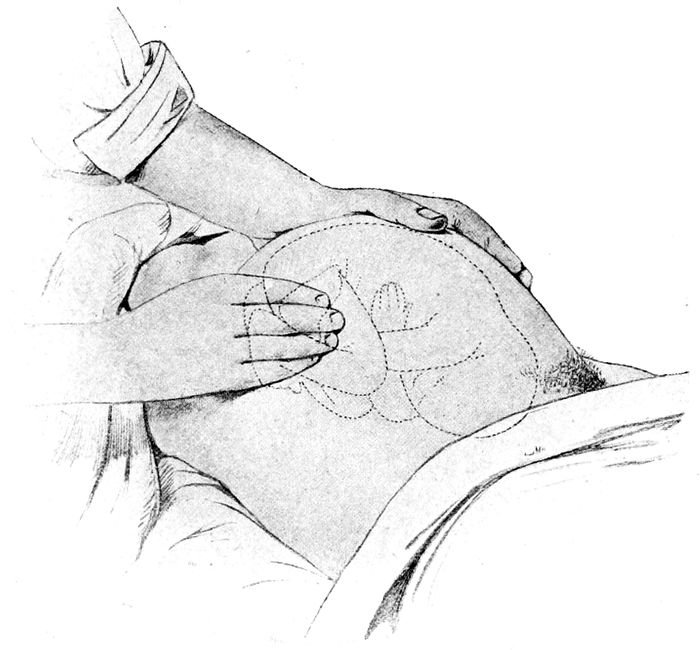

| 54. |

Palpation. What is in the fundus? |

135 |